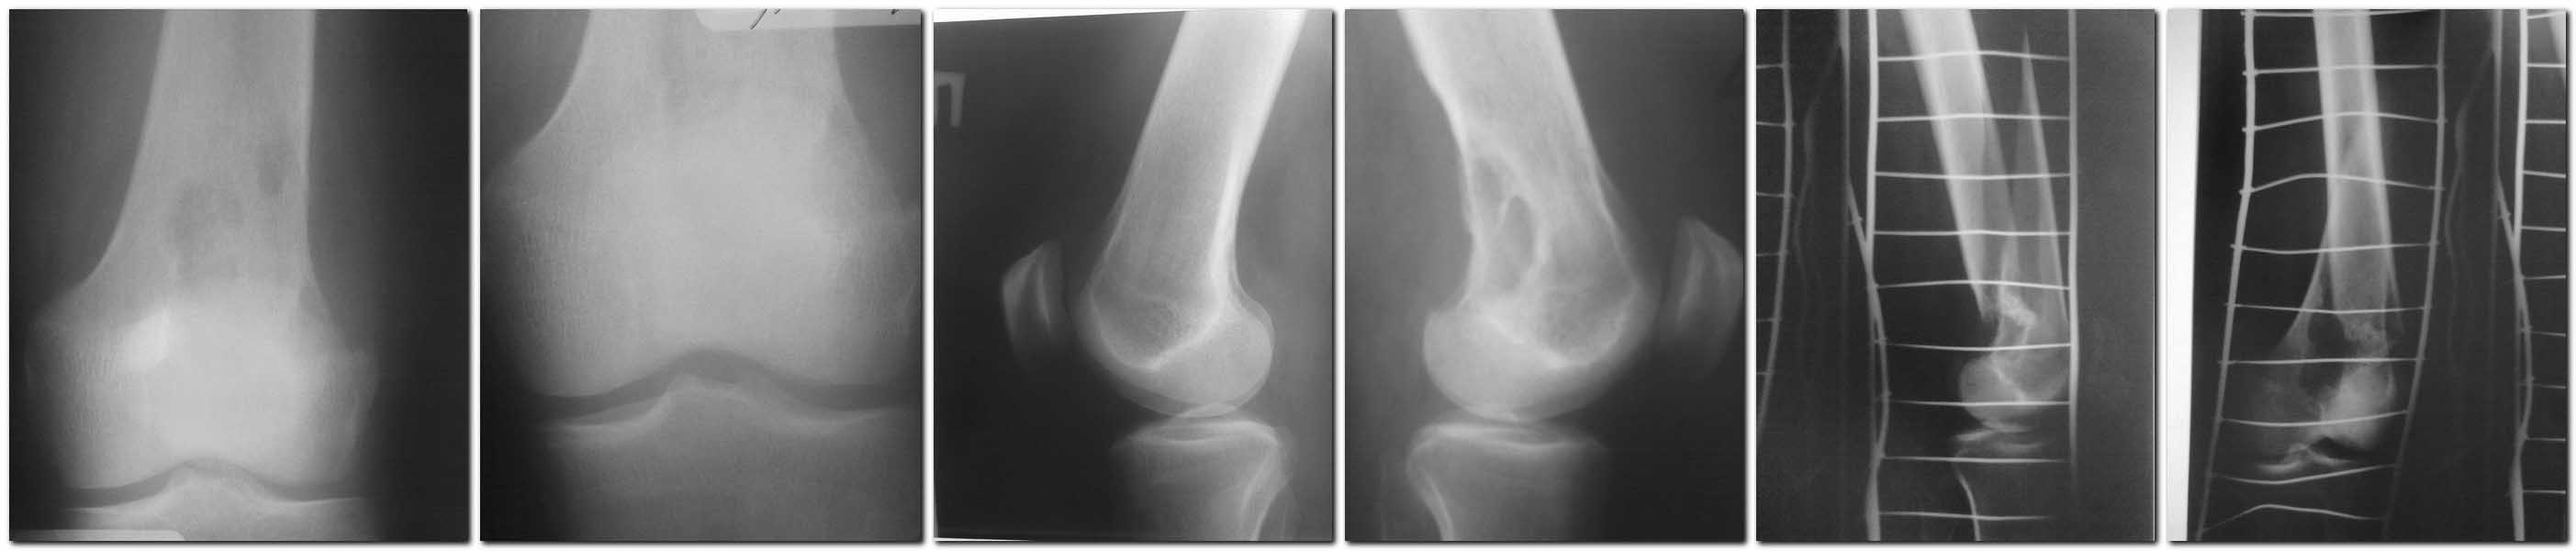

Основной: МКБ -10 (S 72.4) Закрытый патологический косо-вертикальный перелом нижней трети левой бедренной кости со смещением.

Сопутствующий: Хондробластома дистального метаэпифиза левой бедренной кости?

В анамнезе: со слов больного была травма в июне 2011 – ударил кувалдой под колено. Были ноющие боли. В декабре 2011 сел на корточки услышал щелчок в области коленного сустава снаружи, при вставании резкая боль. Боль по утрам, после ходьбы боли уменьшались. 25.02.12. – обратился на прием к хирургу с жалобами на боль в колене. Сделаны рентгенснимки – определили образование дистального метаэпифиза левого бедра, больной записан на КТ коленного сустава на 11.03.12.

R-графия (28.02.12.) левого бедра: косо-вертикальный перелом на уровне дистального метаэпифиза с угловым смещением кпереди дистального фрагмента. В дистальном метаэпифизе визуализируется неправильной формы образование негомогенной структуры, с кистовидной перестройкой – остеома? ЭЭД 0,1 мзв